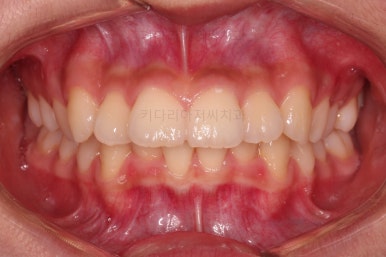

1. 초진 시 입안의 모습 평가

부산치아교정치과 키다리아저씨치과에 처음 내원했을 당시의 입 안의 모습입니다.

전반적으로 윗니가 나와있는 양상이고요.

앞니는 뻐드러져 있네요.

아래 앞니는 위로 솟구쳐 올라서 윗니 뒤쪽을 강하게 치고 있는 과개교합 양상이었고요.

위아래 앞니쪽이 삐뚤어져 있는 상태였습니다.